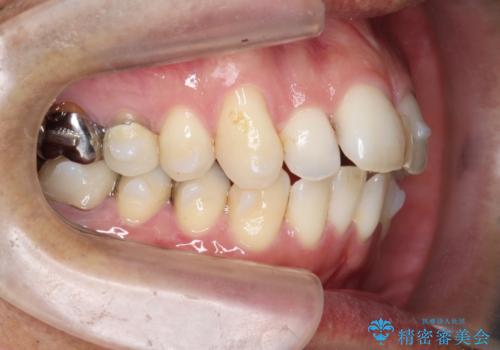

- 突き出た前歯の角度の改善と虫歯治療の改善を求めて来院されました。

虫歯を除去したのち、マウスピース矯正治療を行い、歯並びやがたつきを改善したのち、セラミックに置き換えることで審美性の向上を計画します。